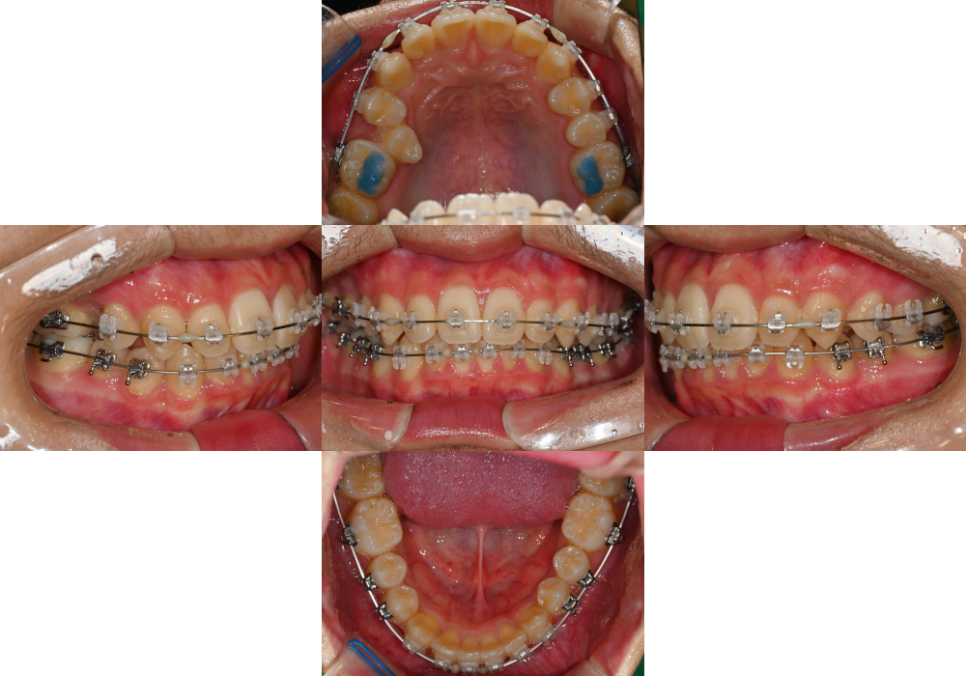

23.09.08

이소맹출된 오른쪽 위 작은 어금니 하나를

제외한 자연치 겉면에

클리피씨 브라켓을 부착했습니다.

삐뚤 빼뚤한 치열을

1차로 배열합니다.

24.01.22

치열이 1차적으로 개선되었을 때

오른쪽 위 작은 어금니가

이동될 수 있는 공간을 만들어 주는데요.

이후 미니 스크류를 식립하여

오픈 코일 스프링으로 인해

오른쪽 전치부의 치열이

이동되지 않도록 고정합니다.